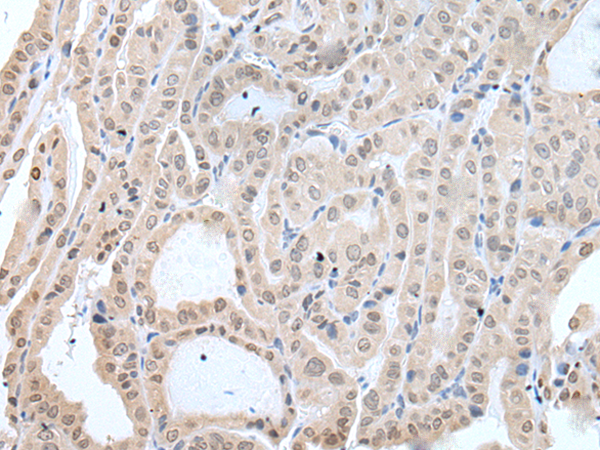

分类: 科研抗体货号: P12761别名: DIRA; IRAP; IL1F3; IL1RA; MVCD4; IL-1RN; IL-1ra; IL-1ra3; ICIL-1RA应用: IHC反应种属: Human